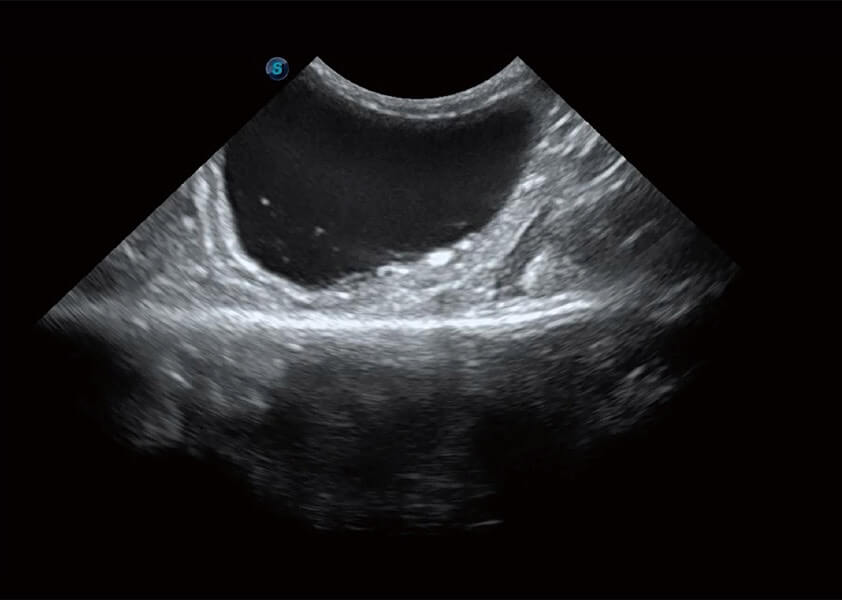

(猫)膀胱结晶